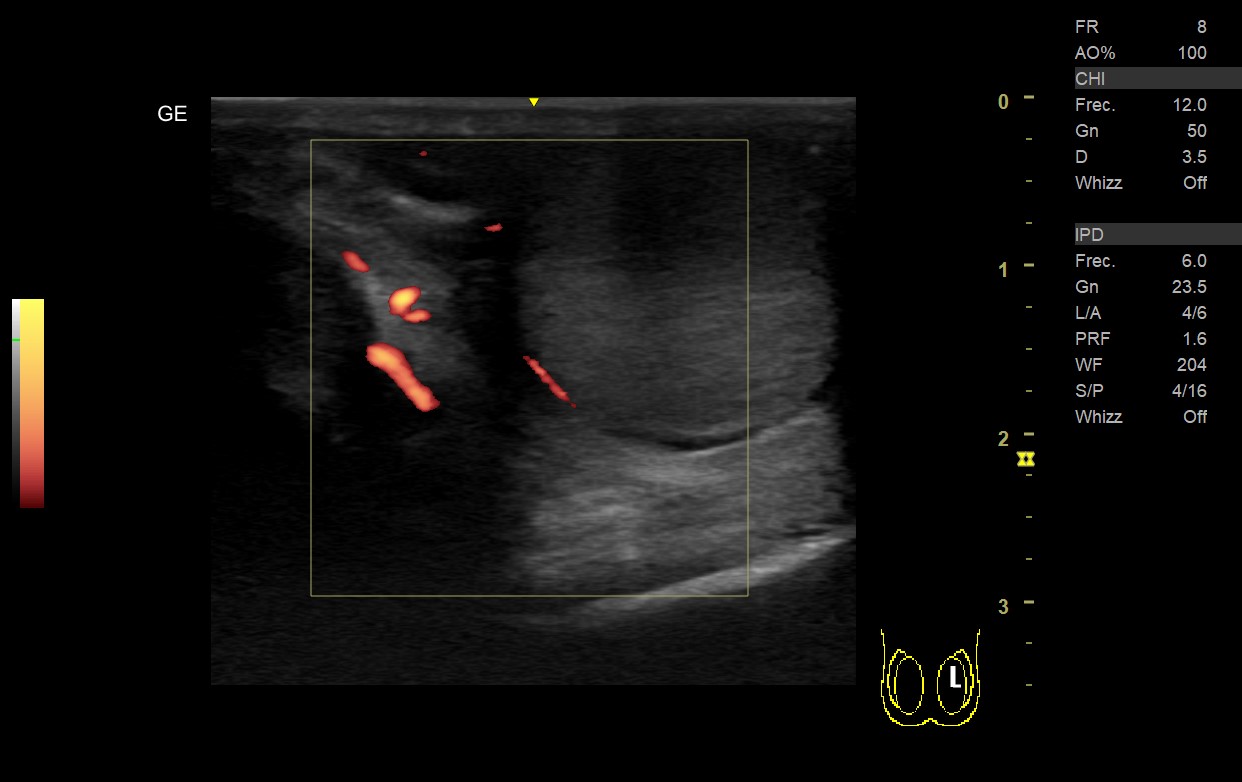

• Teste derecho: aumento de volumen con ecogenicidad heterogénea (áreas más hipoecogenicas), sin captación Doppler color ni power en teste o epidídimo derecho y presencia de líquido en bolsa escrotal.

• Teste izquierdo: volumen y ecogenicidad homogénea con captación Doppler en teste y epidídimo, ausencia de hidrocele.

Al realizar la ecografía, destaca la ausencia de captación Doppler lo cual nos inclina a un diagnóstico de Torsión testicular, ya que a nivel ecográfico la epididimitis presentaría una mayor vascularización y flujo con Doppler.